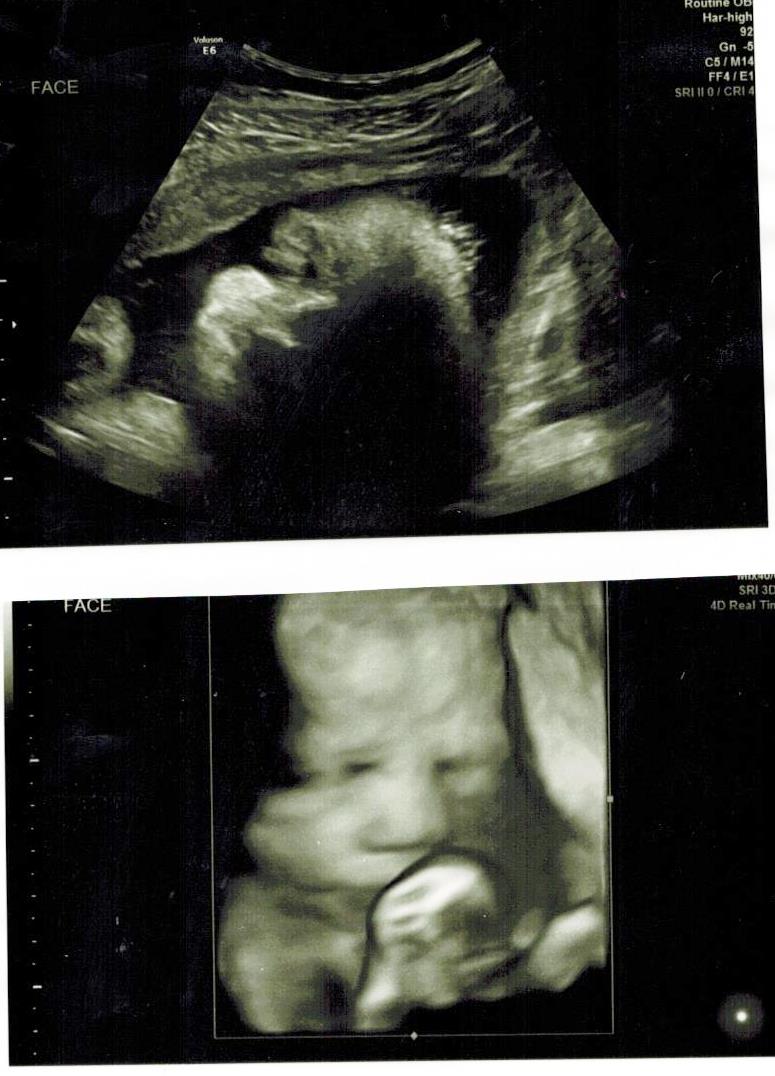

Finally had my follow up u/s to check on baby's kidneys and my low-lying placenta and got great news on both. Placenta has moved up and is completely out of the way now and baby's kidneys look a lot better. Her right kidney is normal now and the left one is only mildly dilated. Baby is also measuring almost 2 weeks ahead at 3 lbs 15 oz! OB said this would be no small baby (yikes!). She still wants to do one last u/s at 36 weeks to check on growth and make sure baby's kidney is completely fine so we'll get a final look at baby in a few weeks.

We got a couple pics of her too. Both here are of her face, one 3D and one 2D.